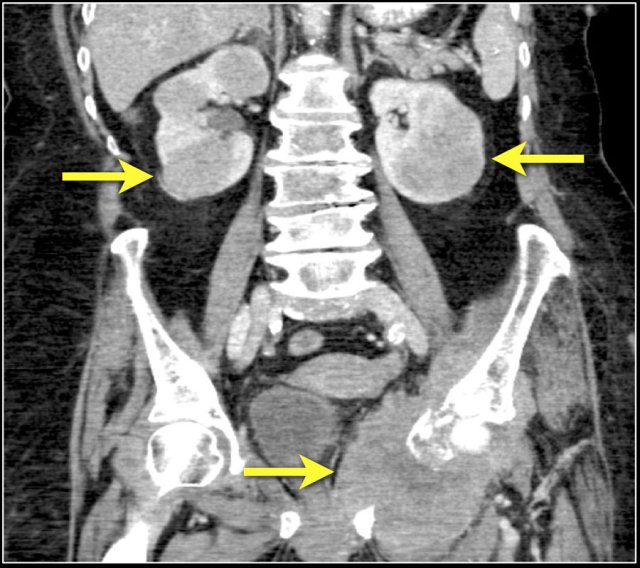

Here a patient with lung cancer.

There is a metastasis in the left kidney and there are multiple lymph node metastases (arrows).

If this was the only presentation, it would be difficult to differentiate from a renal cell carcinoma with lymph node metastases.